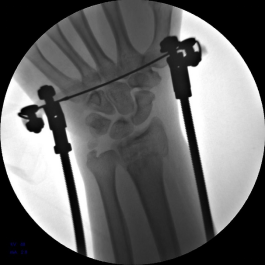

2.安装外固定架,调节螺母纵向牵拉,初步恢复桡骨高度

3.背侧穿针撬拨,继续恢复桡骨高度

4.安装六轴机器人导向器并包裹无菌巾,摆放合适体位。

5.使用执行器夹持克氏针,于掌侧穿针,撬拨骨块并使用六轴机器人固定针末端以维持撬拨位置。

6.六轴机器人撬拨骨块过程

7.手术完毕,复位满意